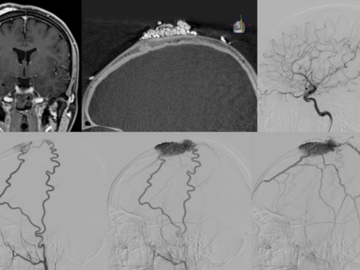

Test yourself with these two Cases of the Week